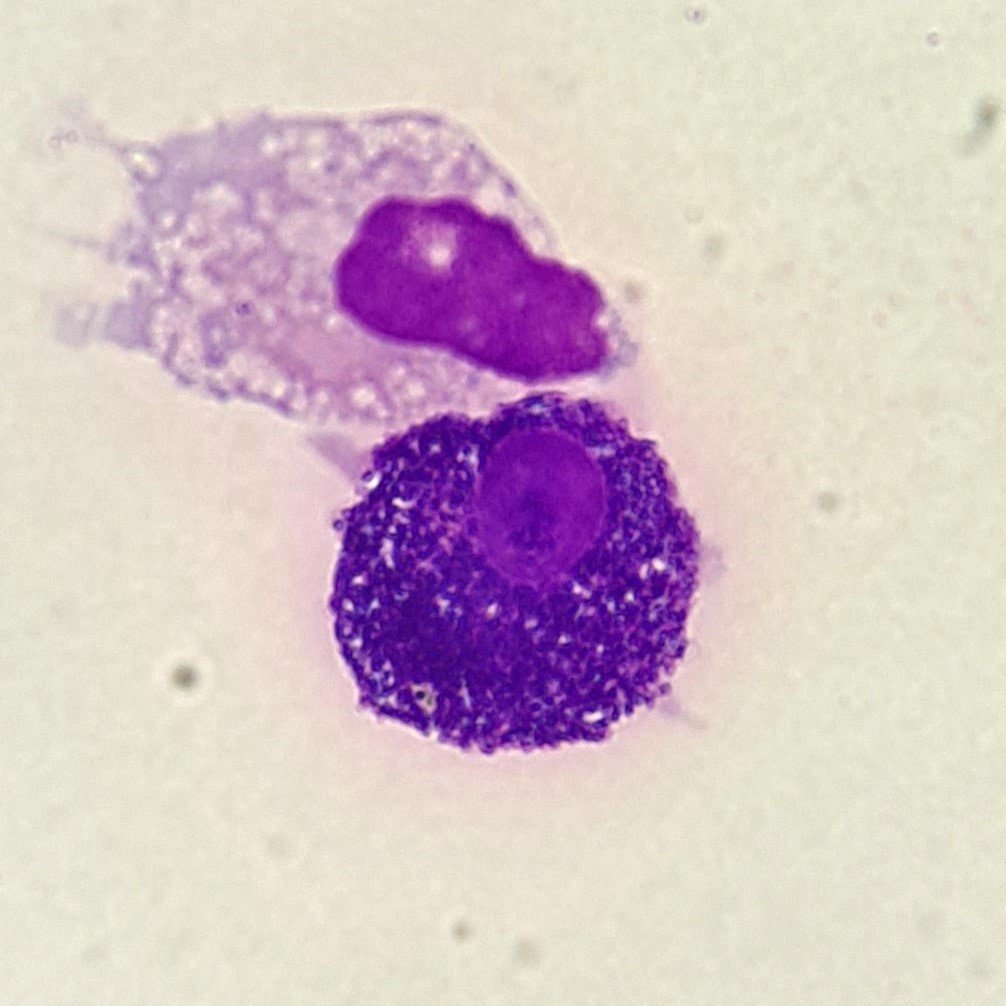

Mesothelial cells are described as having a “fried egg” appearance. They have a round to oval nucleus with smooth borders and evenly distributed chromatin. Nucleloli are usually present. Mesothelial cells may also be multinucleated.

Macrophages are about the same size as mesothelial cells, so the two can often be confused. Macrophages can usually be differentiated by the presence of vacuoles and a lacey chromatin. If both cell types are present and differentiation is difficult, take a look around the slide to get an idea of each kind of morphology before starting a differential.